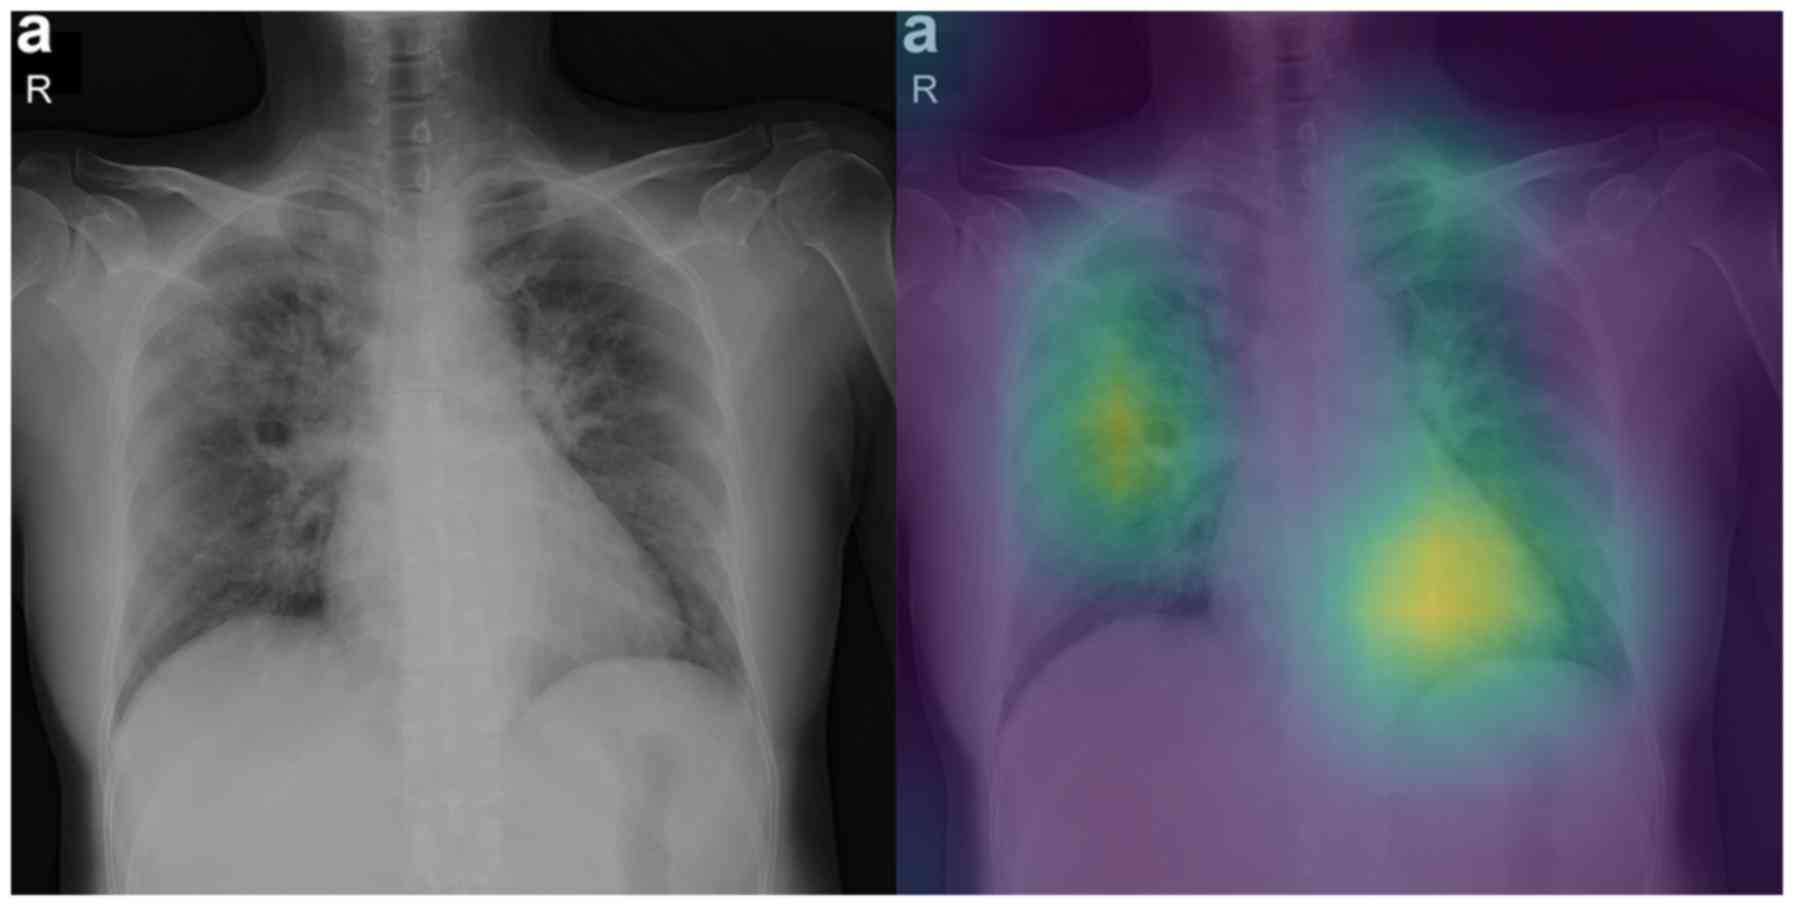

Interpretable artificial intelligence framework for COVID‑19 screening on chest X‑rays

COVID-19 has led to an unprecedented healthcare crisis with millions of infected people across the globe often pushing infrastructures, healthcare workers and entire economies beyond their limits. The scarcity of testing kits, even in developed countries, has led to extensive research efforts towards alternative solutions with high sensitivity. Chest radiological imaging paired with artificial intelligence (AI) can offer significant advantages in diagnosis of novel coronavirus infected patients. To this end, transfer learning techniques are used for overcoming the limitations emanating from the lack of relevant big datasets, enabling specialized models to converge on limited data, as in the case of X‑rays of COVID‑19 patients. In this study, we present an interpretable AI framework assessed by expert radiologists on the basis on how well the attention maps focus on the diagnostically‑relevant image regions. The proposed transfer learning methodology achieves an overall area under the curve of 1 for a binary classification problem across a 5‑fold training/testing dataset.